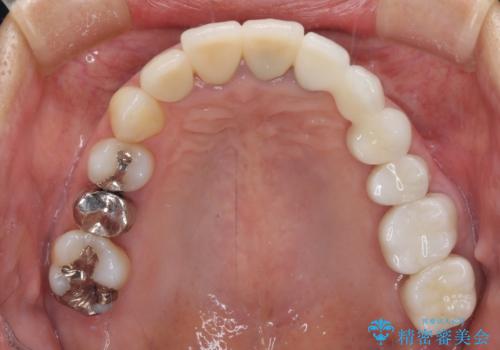

仮歯に置き替え、歯周外科処置(APF、歯肉弁根尖側移動術)による歯周ポケット除去を行った後に、オールセラミッククラウンにて補綴することとしました。

歯周外科処置により歯周ポケットを除去することができ、クラウン装着後はブラッシング時の出血や歯肉の腫れが気にならなくなりました。